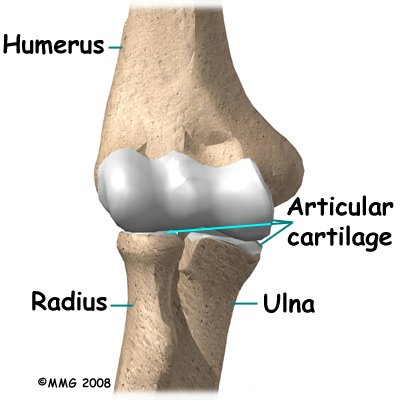

The bones of the elbow are the humerus (the upper arm bone), the ulna (the larger bone of the forearm, on the opposite side of the thumb), and the radius (the smaller bone of the forearm on the same side as the thumb). The elbow itself is essentially a hinge joint, meaning it bends and straightens like a hinge. Most people don’t realize that there is a second joint where the end of the radius (the radial head) meets the humerus. This joint is complicated because the radius has to rotate so that you can turn your hand palm up and palm down. At the same time, it has to slide against the end of the humerus as the elbow bends and straightens. The joint is even more complex because the radius has to slide against the ulna as it rotates as well. As a result, the end of the radius at the elbow is shaped like a smooth knob with a cup at the end to fit on the end of the humerus. The edges are also smooth where it glides against the ulna.

The elbow itself is essentially a hinge joint, meaning it bends and straightens like a hinge. Most people don’t realize that there is a second joint where the end of the radius (the radial head) meets the humerus. This joint is complicated because the radius has to rotate so that you can turn your hand palm up and palm down. At the same time, it has to slide against the end of the humerus as the elbow bends and straightens. The joint is even more complex because the radius has to slide against the ulna as it rotates as well. As a result, the end of the radius at the elbow is shaped like a smooth knob with a cup at the end to fit on the end of the humerus. The edges are also smooth where it glides against the ulna.

Articular cartilage is the material that covers the ends of the bones in a joint. Articular cartilage can be up to one-quarter of an inch thick in the large, weight-bearing joints. It is a bit thinner in joints such as the elbow, which don't support weight. Articular cartilage is white, shiny, and has a rubbery consistency. It is slippery, which allows the joint surfaces to slide against one another without causing any damage. In the elbow, articular cartilage covers the end of the humerus, the end of the radius, and the end of the ulna.